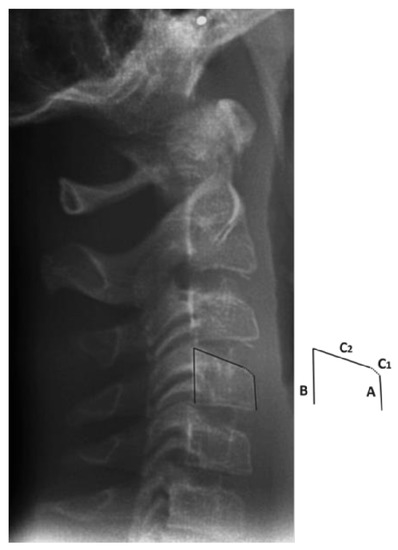

- Cameriere, R.; Giuliodori, A.; Zampi, M.; Galic, I.; Cingolani, M.; Pagliara, F.; Ferrante, L. Age estimation in children and young adolescents for forensic purposes using fourth cervical vertebra (C4). Int. J. Leg. Med. 2015, 129, 347–355. [Google Scholar] [CrossRef]